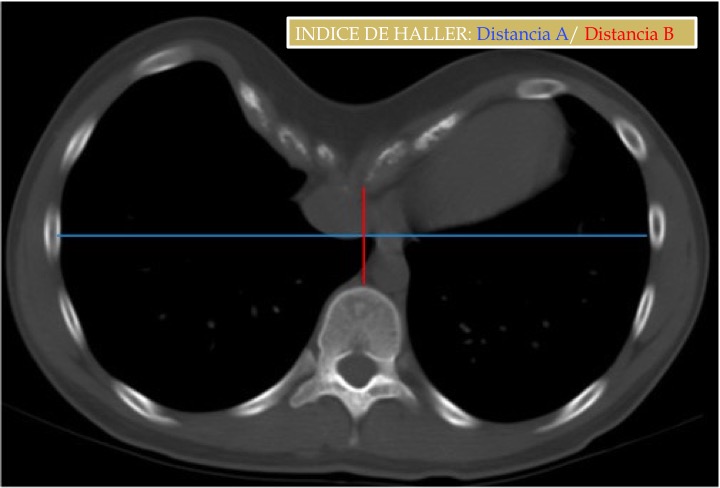

Índice de Haller:

- Medio: 3,2

- Moderado: 3,2-3,5

- Severo: > 3,5 (cirugía).